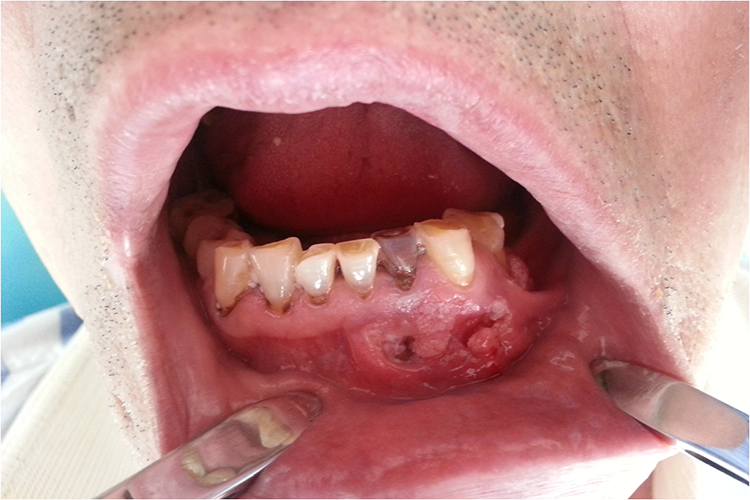

囊肿如继发感染,可有局部红肿、触压痛甚至脓肿形成,并可伴有发热等。巨大的颌骨囊肿可致牙松动、移位、脱落及咬合紊乱,影响进食。

颌骨囊肿因拔牙、损伤、长大等使囊肿破裂向口腔内破溃时,囊内多有草黄色或草绿色液体流出;如为角化囊肿,则可见似皮脂样物质。囊肿破裂后常造成口腔感染、异味。